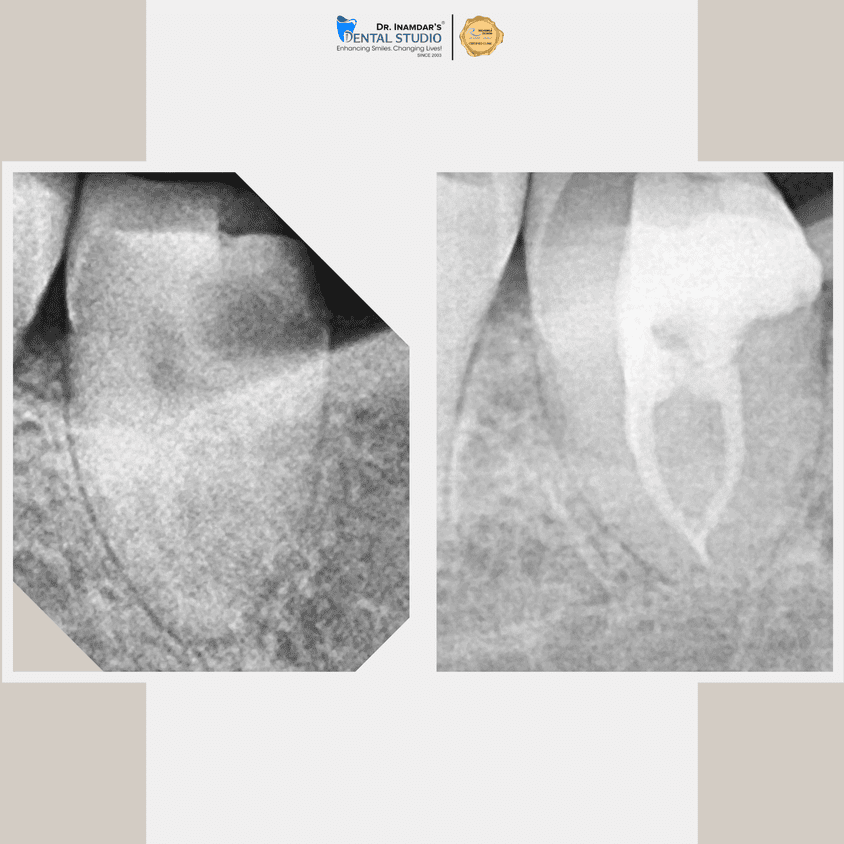

We begin with a detailed dental examination and digital X-rays to identify the source of infection.

Signs that you may need a root canal include persistent tooth pain, sensitivity to hot or cold, swelling around the tooth, or darkening of the tooth. Your dentist can diagnose the need for a root canal through a thorough examination and x-rays.